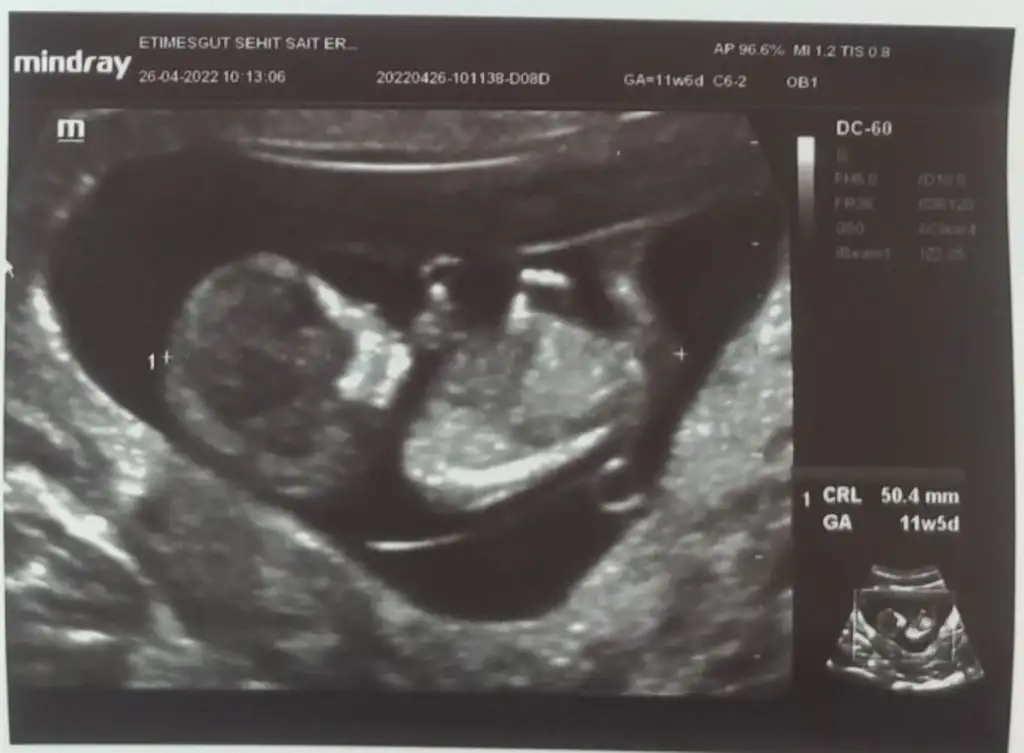

paşa gibiEki Görüntüle 3084920 11+6 Karından ultrason![]()